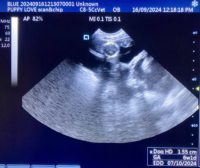

Mobile Ultrasound Pregnancy Scanning and Microchipping Services

Puppy Love scan and chip

Gallery